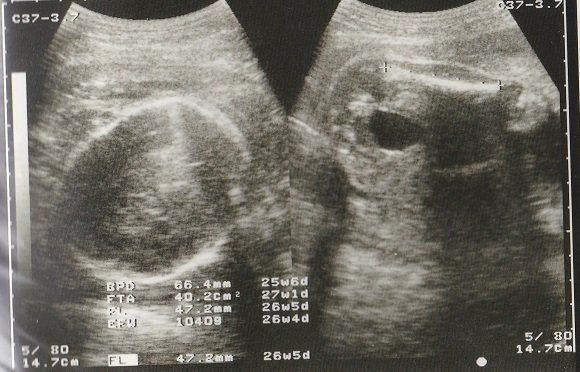

妊娠26週目のエコー写真 男の子であることが判明

左側のエコー画像に、男の子のシンボルが写っています。人によっては、生まれるまで男の子か女の子か告げて欲しくないという方もいらっしゃるようですが、私の場合、お医者さんに何も聞かれずに「男の子ですね」と言われました。

左側は頭の画像。赤ちゃんの頭もだいぶ大きくなりました。